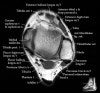

발목 관절의 MRI 단면 영상

- Sagittal section

Bones and marrow

Joint fluid

Talar dome

Subtalar joints

Achille's tendon

Sinus tarsi

Plantar fascia